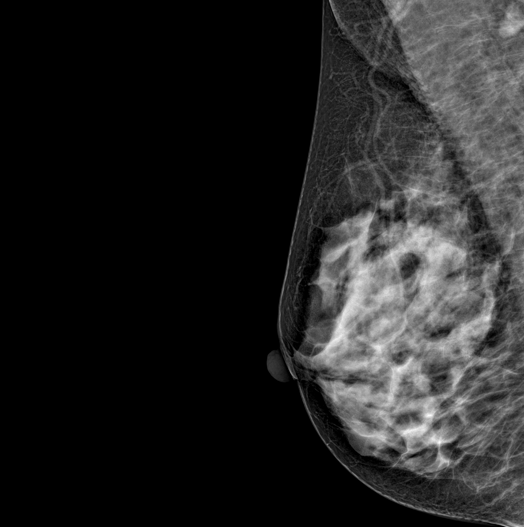

DBT (Digital Breast Tomosynthesis)

The X-ray tube moves on the breast and takes high-definition, high-resolution images with high contrast from various angles.

The images are reconstructed in 3D TO Provide accurate information about the location and condition of the lesion